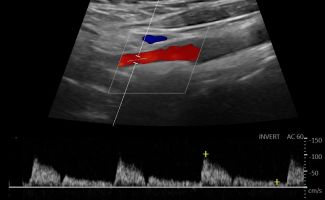

- Έγχρωμο Doppler: Αξιολογεί την ταχύτητα και την κατεύθυνση της ροής του αίματος, προσδιορίζοντας την ύπαρξη και το ποσοστό στένωσης των αρτηριών.

- Παλμικό Doppler: Παρέχει πληροφορίες για τις διακυμάνσεις της ροής του αίματος, βοηθώντας στην αναγνώριση πιθανών αιμοδυναμικών διαταραχών.